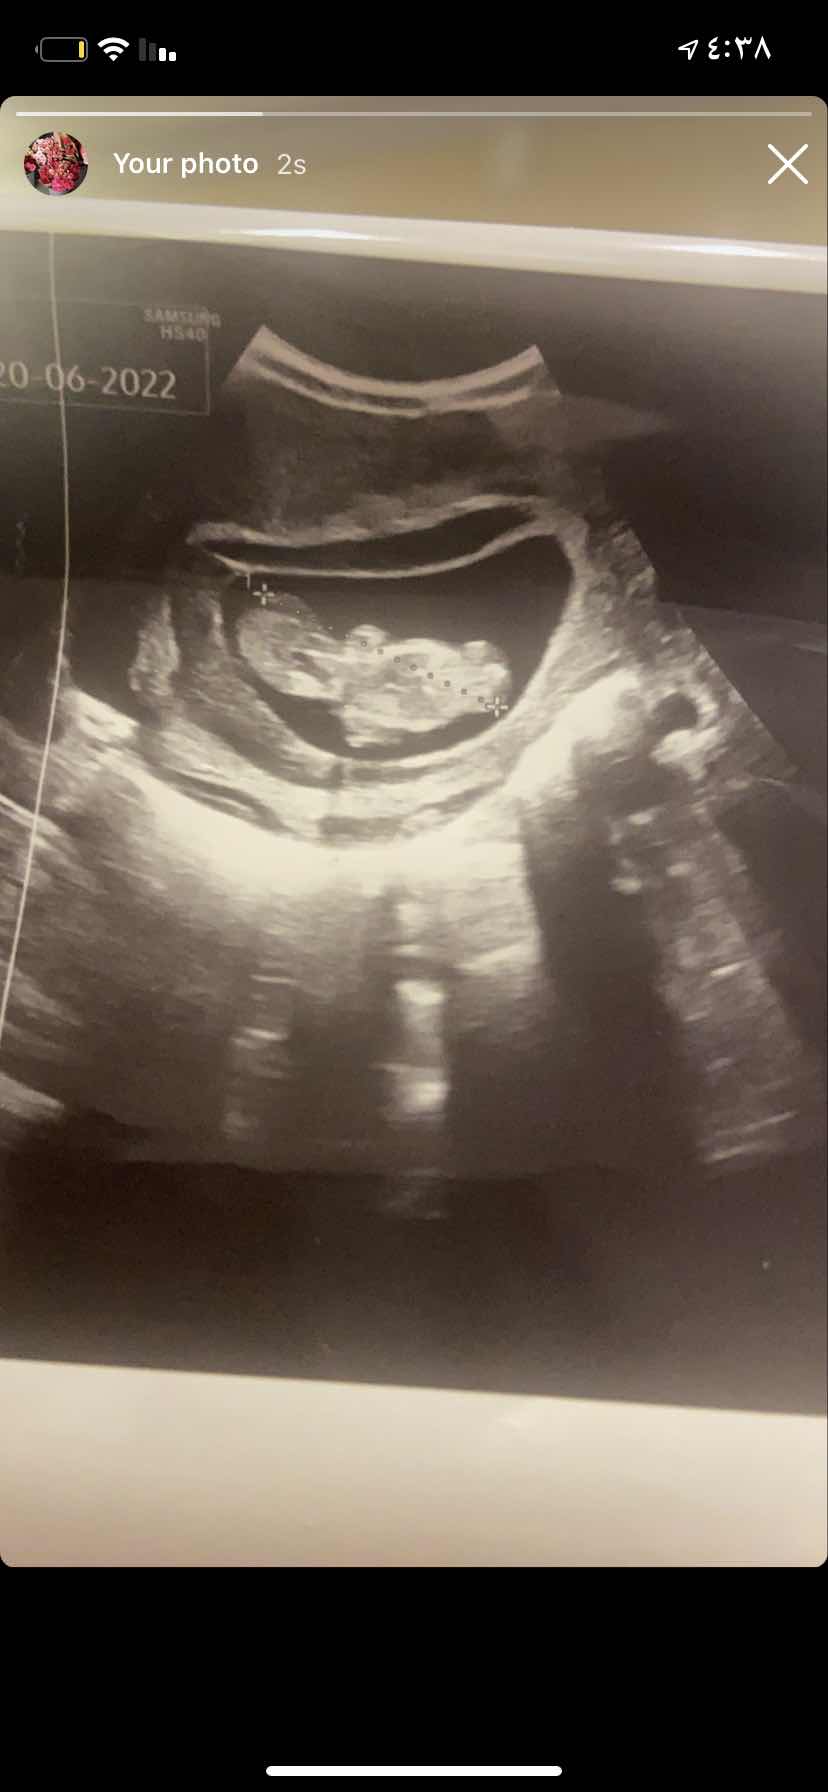

انفصال المشيمه ماسببه وطريقه علاجه